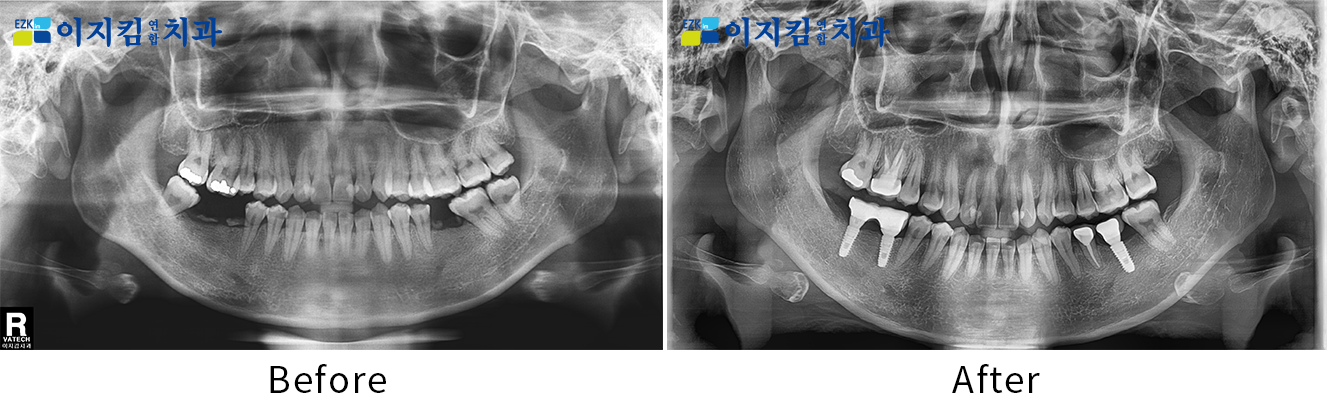

ÀÓÇöõÆ® Àü ¡¤ ÈÄ »çÁø

[

Á¶È¸¼ö : 3100

]